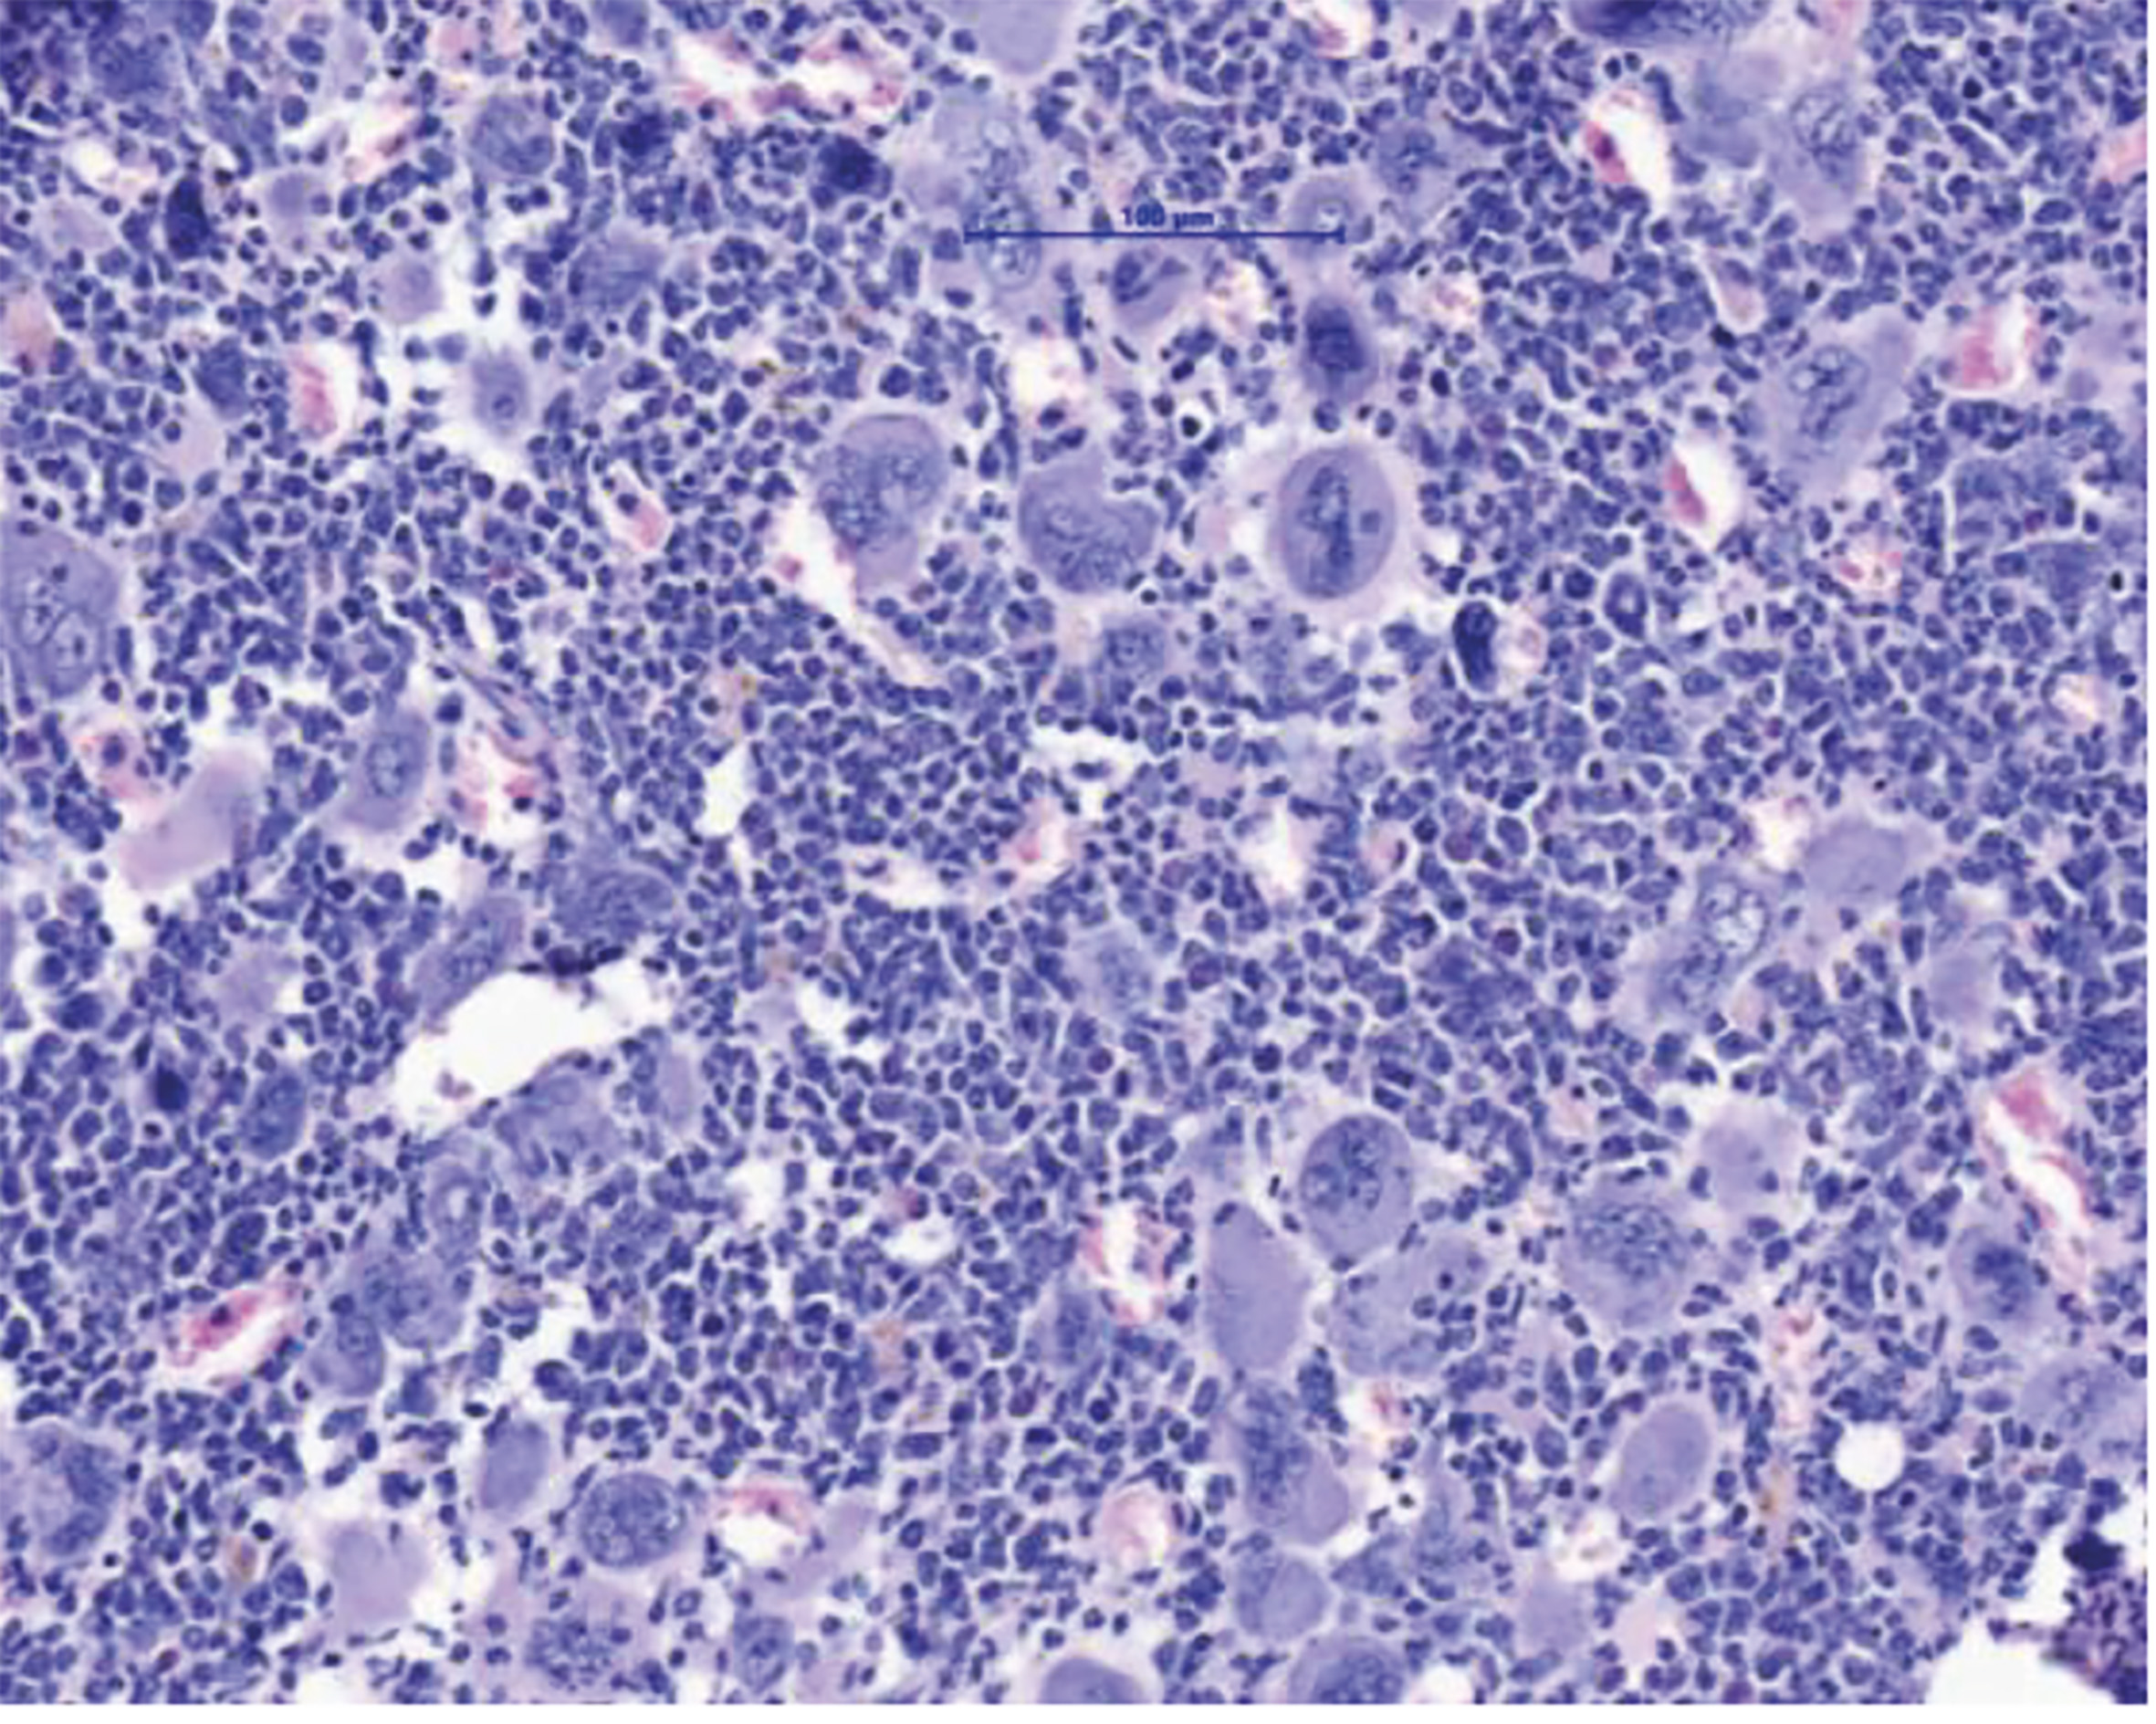

Innsbruck, Bonn am 2.12.2025: Myeloproliferative Neoplasien (MPN) sind Blutkrebserkrankungen, die durch eine Überproduktion von Blutzellen gekennzeichnet ist. Diese Erkrankungen treten in der Regel ab einem Alter von 60+ Jahren auf und können über lange Zeit gut kontrolliert werden. Gefährlich werden MPN vor allem nach dem Übergang in eine Myelofibrose – eine lebensbedrohliche Vernarbung des Knochenmarks. Eine allogene Stammzelltransplantation bietet für die betroffenen Patient:innen bis heute die einzige Aussicht auf Heilung. „Wir brauchen dringend neue Therapiekonzepte. Eine Stammzell-Transplantation ist für viele Patient:innen aufgrund ihres hohen Alters oder wegen Begleiterkrankungen mit zu hohen Risiken verbunden“, erklärt Dominik Wolf, Direktor der Univ.-Klinik für Innere Medizin V (Hämatologie und Onkologie) an der Medizinischen Universität Innsbruck, den Hintergrund einer soeben im Fachjournal Nature Communications hochrangig publizierten Forschungsarbeit, die er konzipiert und gemeinsam mit Lino Teichman und Miriam Körber vom UKBonn durchgeführt hat. „Wir zeigen in dieser Arbeit ein mögliches neues Therapiekonzept auf, das man klinisch weiterentwickeln sollte“, sagt Wolf, der gemeinsam mit Lino Teichmann als Letzt- und korrespondierender Autor firmiert. Den Wissenschafter:innen ist es gelungen, das NLRP3-Inflammason im Tiermodell zu hemmen und dadurch deutliche Verbesserungen des Krankheitsverlaufs zu erzielen: Die Knochenmarksvernarbung und die Milzvergrößerung bildeten sich zurück und das Blutbild verbesserte sich.

Konkret haben sich die Autor:innen mit den Mechanismen der Entzündungsreaktion bei MPN beschäftigt, da diese zu vielen klinischen Symptomen und letztlich auch zur Vernarbung des Knochenmarks führt. Das NLRP3-Inflammasom ist ein Sensor für Gefahrensignale, der Entzündungsprozesse im Körper steuert und dessen Bedeutung bereits eingehend bei chronischen Entzündungserkrankungen wie Atherosklerose, Gicht oder auch Diabetes Typ-2 studiert wurde. Bei MPN wird die Entzündung in den bösartigen, aber auch in den begleitenden, noch gesunden Blutzellen von einer genetischen Treibermutation ausgelöst, wobei hier die aktivierende Mutation JAK2V617F eine zentrale Rolle spielt.

„Wir haben eng mit Eicke Latz, dem Leiter des Deutschen Rheuma-Forschungszentrums in Berlin, kooperiert, der uns verschiedenste Tools zur Verfügung gestellt hat. Damit konnten wir zeigen, dass diese Entzündungsfaktoren wirklich in Abhängigkeit von NLRP3 produziert werden. Besonders interessant war, dass wir das NLRP3 genetisch in Knockout-Mäusen und auch mithilfe eines neuartigen und spezifischen NLRP3-inhibierenden Medikaments hemmen konnten“, spricht Wolf einen möglichen Therapieansatz an. Dank IFM-2384, einer Substanz, die ebenfalls von Eicke Latz bereitgestellt wurde, konnte im Tiermodell eine deutliche Verbesserung erzielt werden. „Die Knochenmarksvernarbungen und auch die meistens sehr ausgeprägten Milzvergrößerungen gingen zurück. Wir konnten auch das Blutbild verbessern“, zählt Wolf auf.

In einer tiefergehenden Analyse sahen die Forscher:innen, dass vor allem die Überproduktion der Blutplättchen infolge der NLRP3-Blockade deutlich reduziert wurde. „Das NLRP3-Inflammasom spielt eine große Rolle als Gefahrensensor. Bei akutem Stress – wie z. B. einer Infektion – wird ein Rescue-Mechanismus in unserem Körper angeworfen, in dessen Folge sehr schnell sehr viele Blutplättchen erzeugt werden“, sagt Teichmann. Gemeinsam mit Wolf beschäftigt er sich seit vielen Jahren mit der Regulation von Entzündungsprozessen bei hämatologischen Erkrankungen. „In diesem sehr komplexen Entzündungsgeschehen hat NLRP3 ganz offensichtlich große Bedeutung“, sagt Wolf.